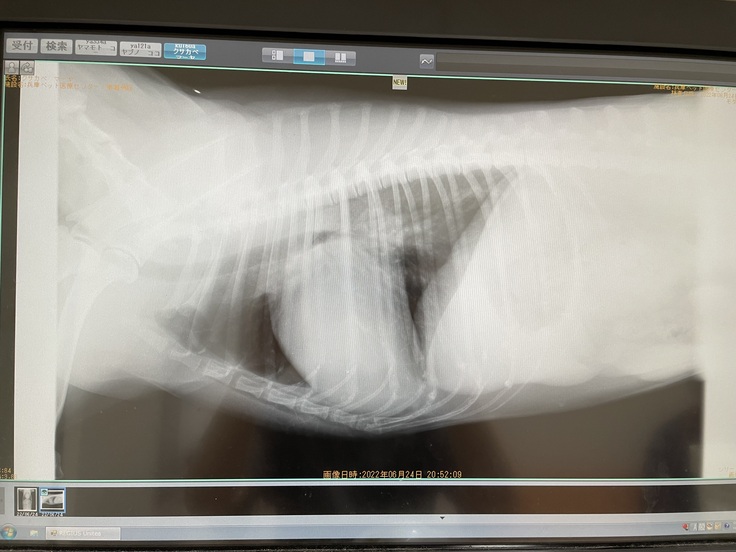

【現在のマーヤの心臓エコー写真】心臓肥大により心臓が気管を押し上げて気道が狭くなっています。

【パンパンに肥大したマーヤの心臓】